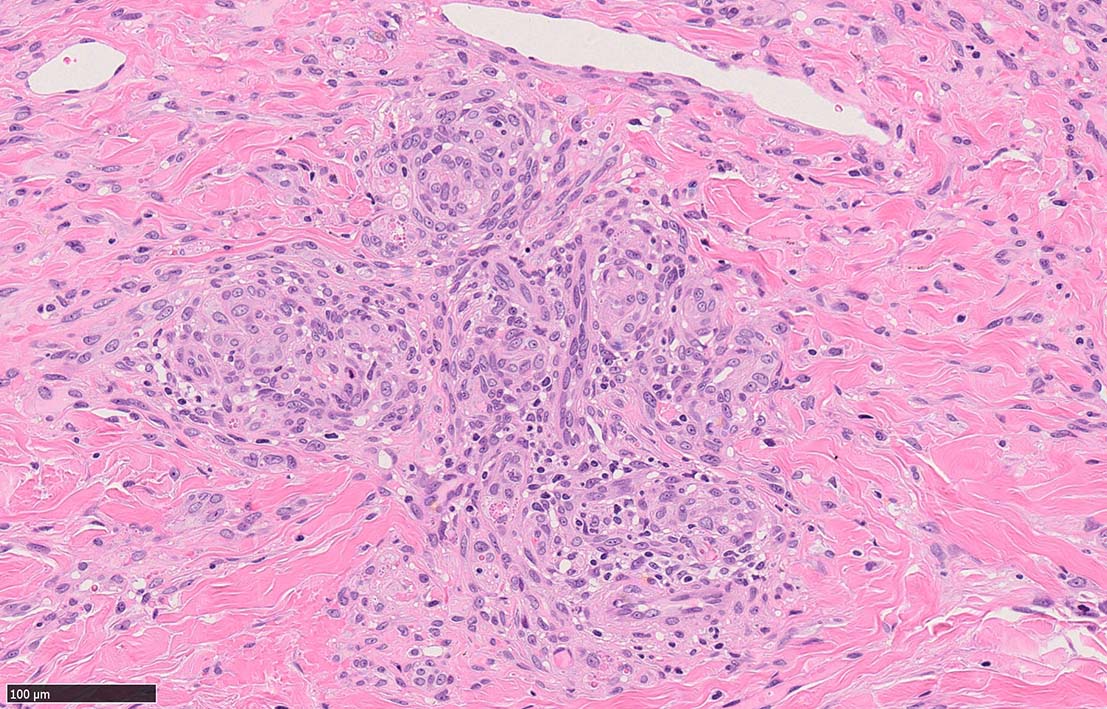

結節性病変の形成

紡錘形細胞が著しく増生し束状に走行する部分と, 内皮細胞様細胞による多数の小管腔構造が巣状にひろがり, 一見, 線維腫と血管腫が混在しているように見える. 一部の症例を除き, これらの増生細胞は異型性に乏しいことが多い.

細血管周囲に血管内皮様の紡錘形細胞が増生, 一部に赤血球をいれた裂隙の形成がある. 細胞の異型はみられず, mitosisの増多もない. hemosiderin-laden macrophageが散在する.

病変は真皮内に現局している. 初期斑状病変に相当すると考えられる. 本例では, 特徴とされる形質細胞浸潤増加はみられない.

参考症例:中部交見会1246: Kaposi's sarcoma 右足内側部皮膚/ 40歳代男性 焼津市立病院 久力 権先生